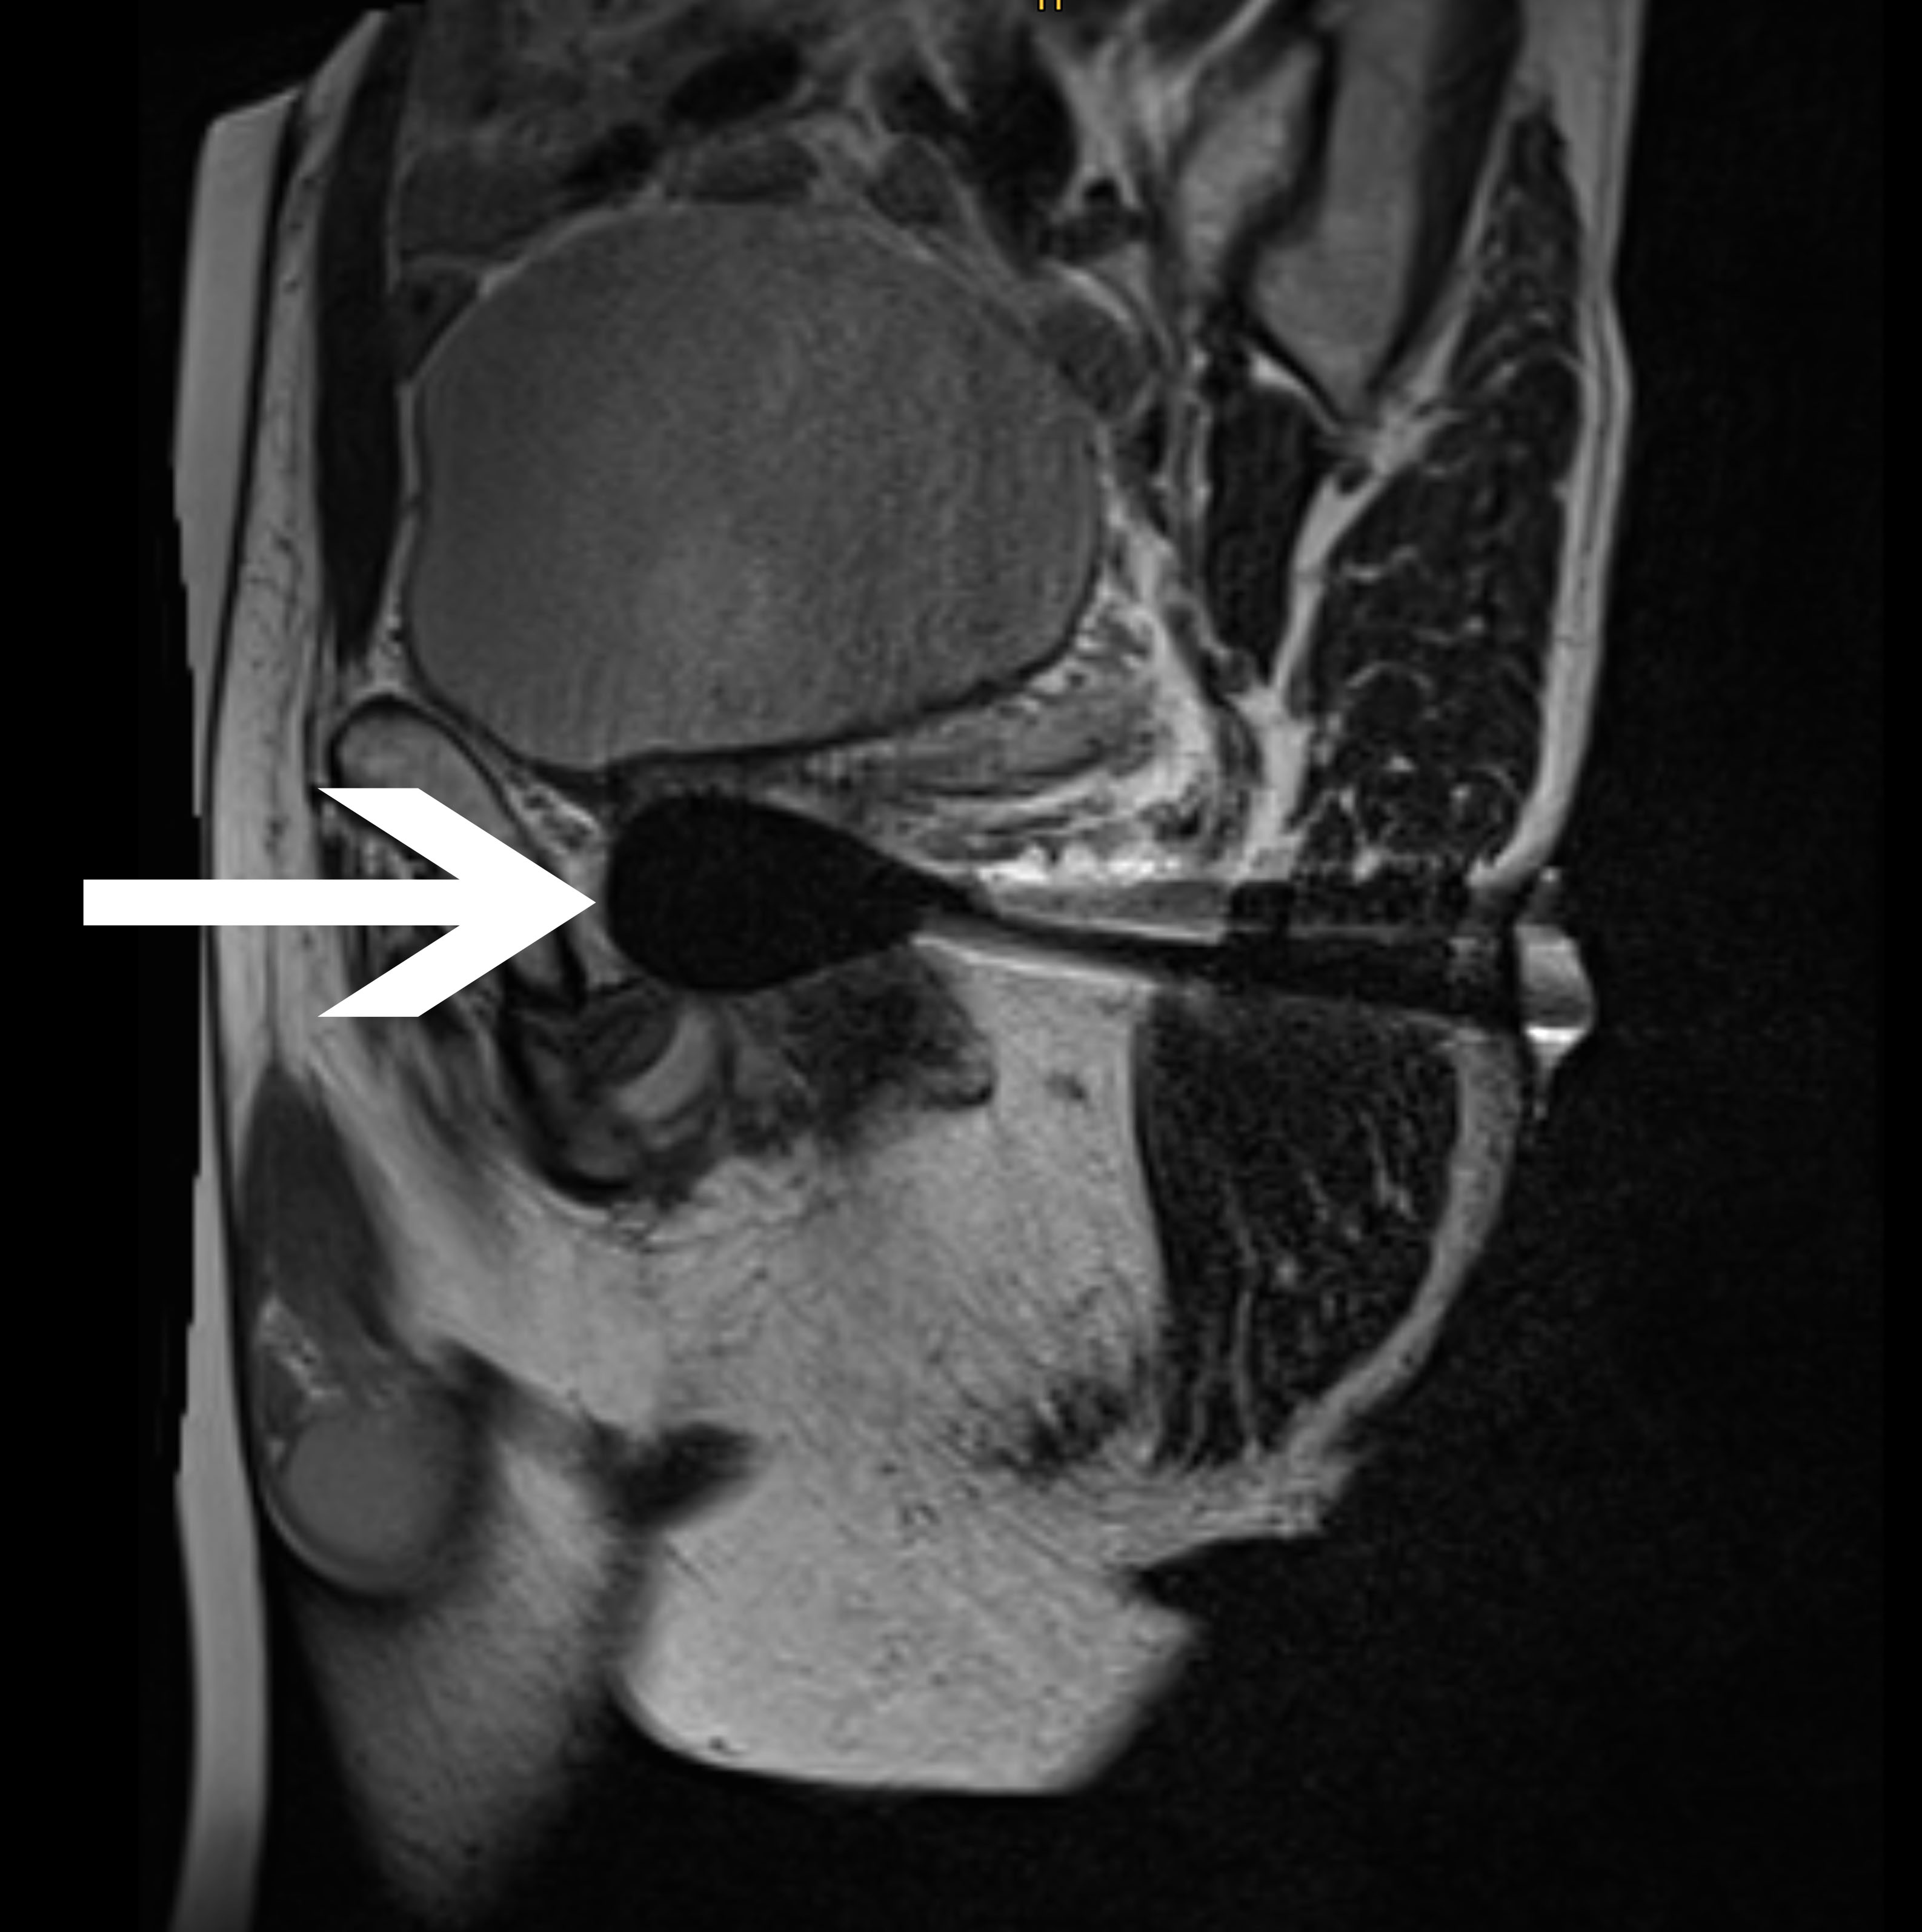

Abb 2:

Periinterventionelles MRT mit

transgluteal positionierten

Kryoablationssonden und dem

anhand des schwarzen

Auslöschungsartefakts erkennbaren

Ablationsareal innerhalb der

Prostata in:

- koronarer Ansicht

- transversaler Ansicht

- sagittaler Ansicht